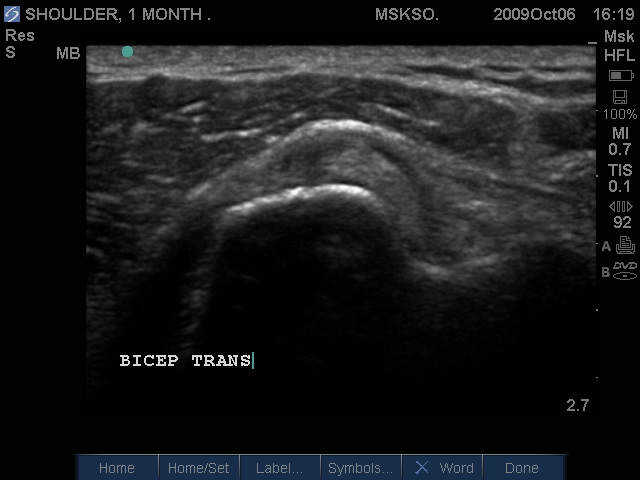

Subluxing Bicep tendon over proximal lesser tuberosity

Splitting Bicep tendon over lesser tuberosity